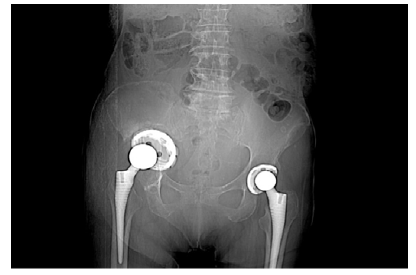

Doente de 80 anos, sexo feminino, com antecedentes pessoais médicos de hipertensão arterial, diabetes mellitus tipo 2, dislipidemia, fibrilhação auricular crónica paroxística, AVC cerebeloso à direita, anemia ferropénica e antecedentes cirúrgicos de laqueação de trompas e cistopexia por laparatomia mediana, prótese de anca bilateral, prótese aorto-aórtica por isquemia crónica dos membros inferiores por doença obstrutiva da aorta abdominal. Por edema assimétrico e impotência funcional do membro inferior direito realizou angio-tomografia computorizada (Angio-TC) pélvica em 11/01 que revelou “extensa trombose da veia ilíaca externa direita, de sugestão aguda (…) migração pélvica do componente acetabular da artroplastia total da coxofemoral direita por loosening com perda parcial da congruência da cabeça femoral”. Coexistem alterações inflamatórias/granulomatosas locais e presença de adenopatias inguinais proeminentes, de provável natureza reativa,” Figura 1 e 2.

Verifica-se protusão do acetábulo à direita, após artoplastia da anca.

Verifica-se intima relação entre os vasos ilíacos e a protusão acetabular

A doente foi internada e operada em 18/01/2021, sem intercorrências, por acetábulo protuso intra-pélvico com compressão dos vasos ilíacos a condicionar trombose venosa profunda. Verificou-se migração pélvica do componente acetabular da prótese total da anca direita, possivelmente a condicionar compressão da veia ilíaca externa. Fez-se remoção do componente acetabular e femoral e ficou internada ao cuidado da Ortopedia.